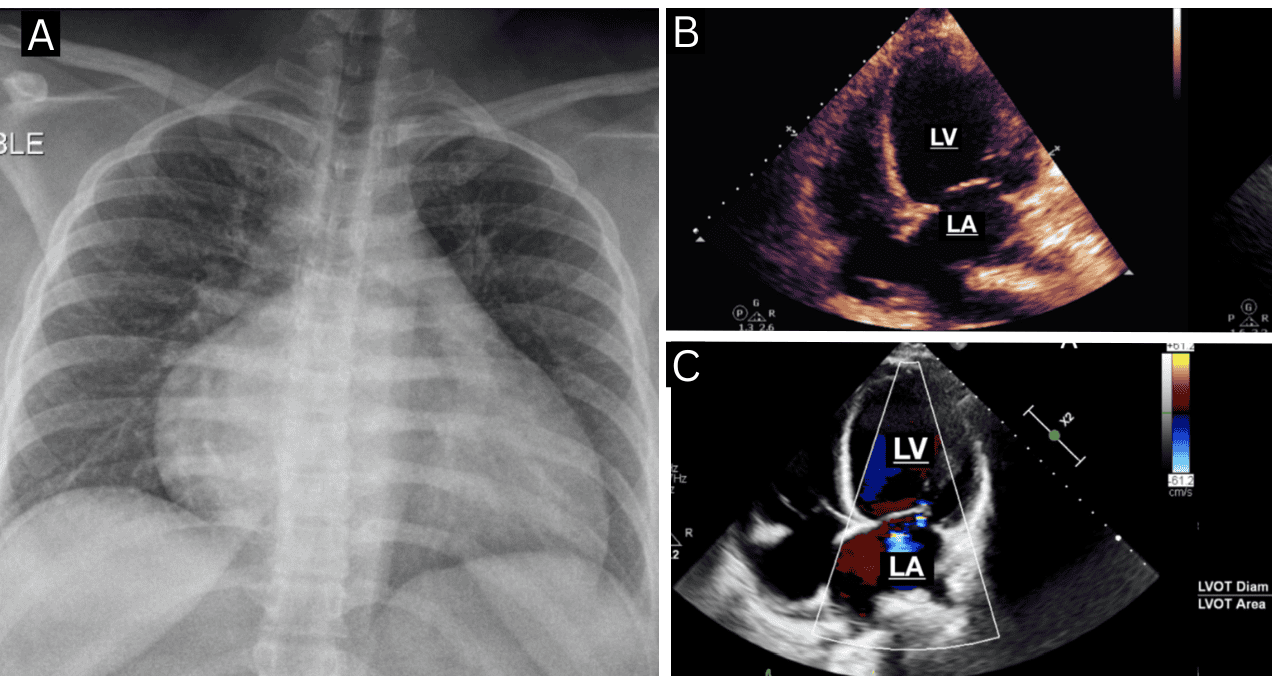

Una radiografía de tórax mostró cardiomegalia y signos de congestión vascular. El ecocardiograma 2D confirmó una dilatación severa del ventrículo izquierdo con fracción de eyección (FEVI) menor al 20 % e hipocinesia global. Los hallazgos de laboratorio indicaron disfunción multiorgánica: elevación significativa de transaminasas (AST: 2092, ALT: 1579), troponinas (3358,91), BNP (1312), lactato (6,28) y creatinina (1,04).